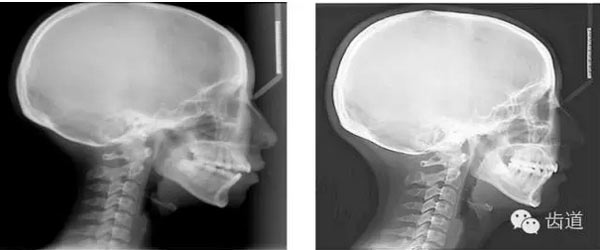

下頜后縮為主要特征的骨性II類,高角,前牙開(kāi)合,上前牙略唇傾,雙側(cè)下頜升支及髁狀突不對(duì)稱,右側(cè)較左側(cè)粗壯,左側(cè)髁狀突外斜面曾有吸收,但現(xiàn)骨白線與皮質(zhì)骨已比較連續(xù),上呼吸道正常。上

頜第三磨牙牙冠較小。

顏面軟組織:面部左右不對(duì)稱,頦部右偏,凸面型,上下唇較厚、略前突,鼻唇角較小,頦唇溝淺,下頜后縮,頦肌緊張,頦部形態(tài)不良

矢狀向:安氏II類,骨性II類,下頜后縮,上前牙唇傾

垂直向:高角,垂直生長(zhǎng)型,前牙開(kāi)合